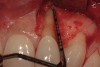

Figure 10  Submarginal flap elevation reveals apical concavity and associated fenestration defect.

Figure 10

Figure 11  Extraction site following grafting, flap suturing, and adaptation and fixation of resorbable collagen membrane.

Figure 11